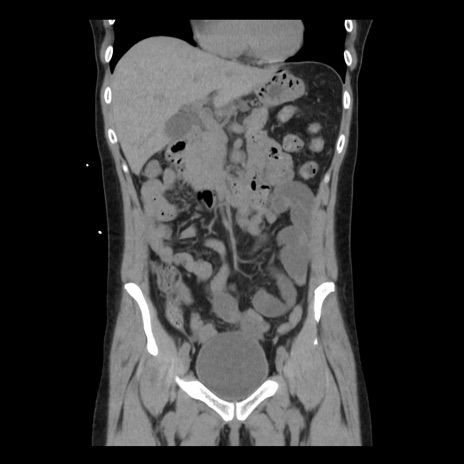

症例10(冠状断像)

【症例】 50歳代女性

【主訴】 腹痛

【現病歴】前日生レバーを食べた。今朝に排便あり。 昼前に突然発症の腹痛を生じ、当院救急外来を受診した。

【既往歴】 子宮筋腫にてで子宮全摘後

【身体所見】 意識清明、腹部:平坦、軟、下腹部やや左を中心に圧痛・反跳痛あり、筋性防御あり

【データ】WBC 7800、CRP 0.07